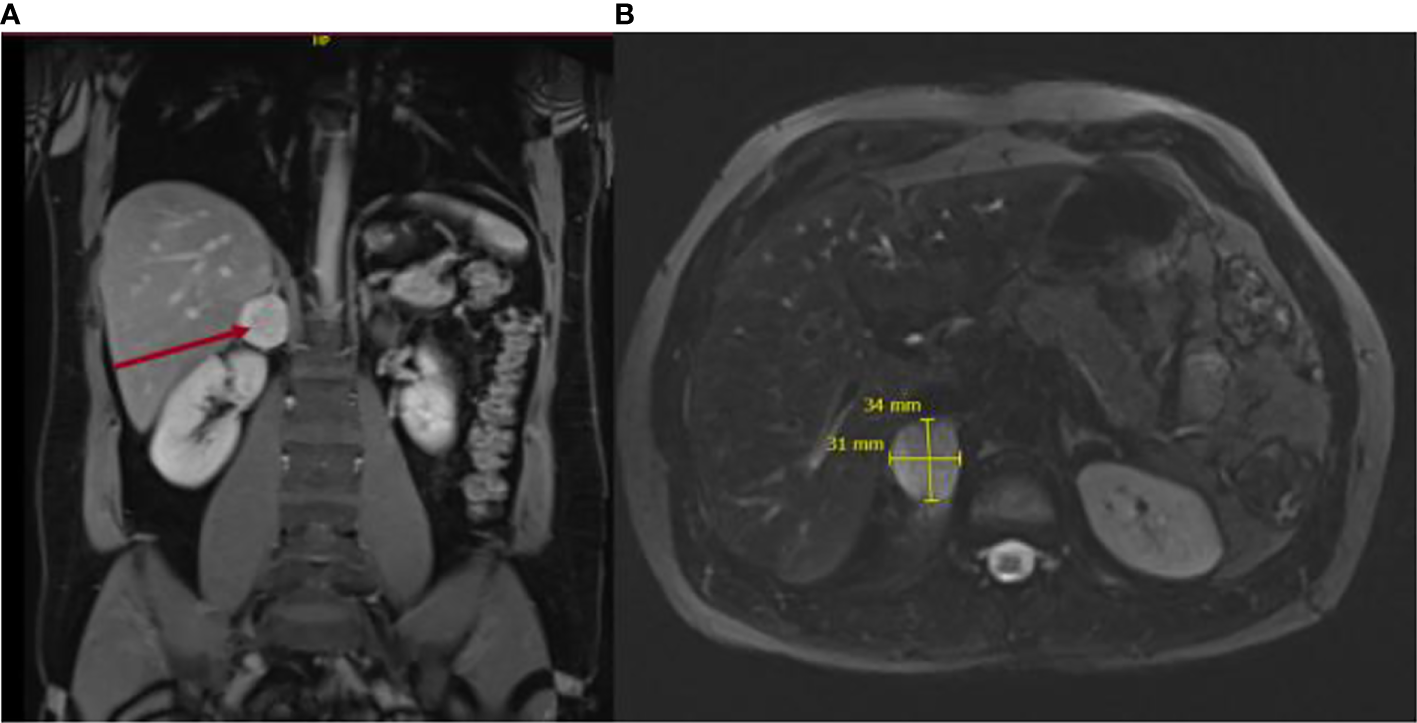

The patient had no history of hypertension and no previous complaints. In December 2020, he was diagnosed with COVID-19 after presenting with typical symptoms, such as persistent cough, as well as headaches, concentration difficulties, and severe fatigue. He also complained further of profuse sweating and general weakness on a daily basis. He denied any medication or drug intake. On the thoracic CT scan, a right inhomogeneous adrenal mass was identified. An abdominal MRI confirmed the right inhomogeneous mass, presenting no signal loss on out-of-phase imaging, findings that raised the suspicion of a catecholamine-producing tumor (Figure 2). Biochemical diagnosis revealed a raised concentration of plasma normetanephrine, and the patient was referred to our endocrine clinic for further investigation.

Figure 2

Magnetic resonance imaging depicting axial diffusion-weighted (A) and coronal views (B) of the 4-cm adrenal mass. .